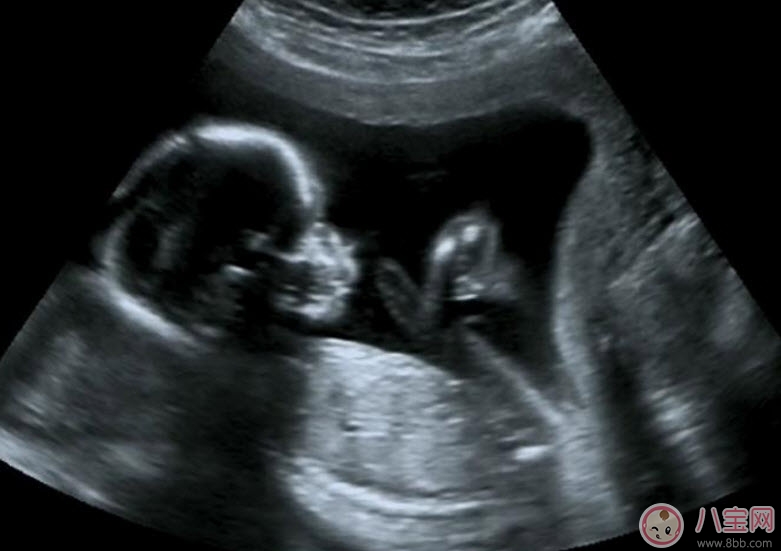

經(jīng)陰道超聲是通過(guò)超聲機(jī)上的特殊探頭而實(shí)現(xiàn)的。在陰道超聲探頭上套上薄膜,將探頭伸入陰道進(jìn)行檢查。由于探頭位置接近子宮和卵巢,圖像清晰分辨率高,檢查結(jié)果較準(zhǔn)確。除此之外,它還有另一個(gè)優(yōu)點(diǎn)是不需要憋尿,相對(duì)節(jié)省時(shí)間,患者感覺(jué)也好。

為監(jiān)測(cè)孕囊的部位、胎兒的生長(zhǎng)發(fā)育情況,降低畸形兒和有缺陷兒的出生率,早孕期陰道B超檢查顯然是很必要的。早孕期做陰道B超檢查有以下幾點(diǎn)好處: